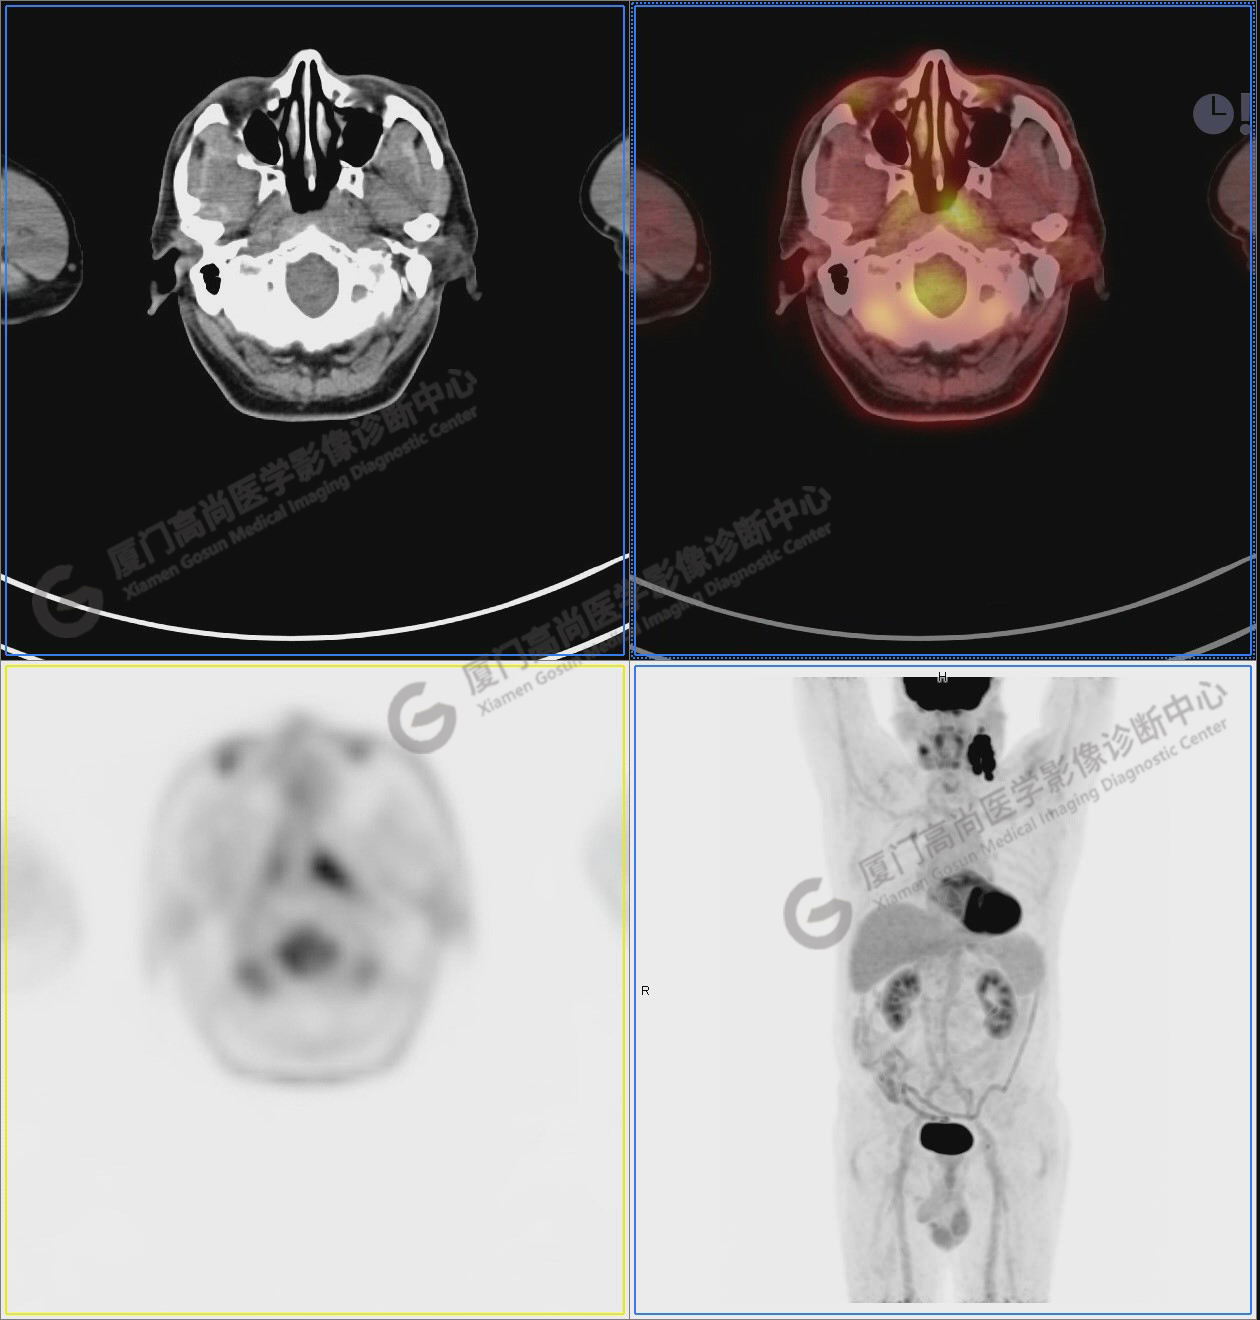

PET/CT影像圖

圖1:PET/CT全身圖像

圖2:雙側(cè)頸部多發(fā)增大淋巴結(jié),代謝不同程度增高,考慮為轉(zhuǎn)移。

圖6-9:鼻咽左側(cè)壁增厚,代謝異常增高,考慮為鼻咽癌

圖6

圖7

圖8

圖9